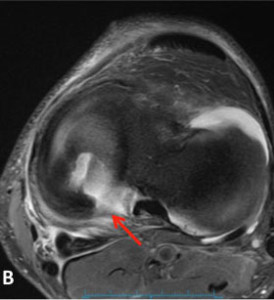

Meniscal Root Tear Meniscal root tears can be seen on coronal, axial and sagittal MRI views. On the sagittal view, as seen in Figure C, there is a “ghost sign” which is indicative of meniscal root tear. A normal, healthy meniscus should look like a dark black triangle; however, as this figure shows the meniscus is much lighter or “ghosted” representing the root tear.